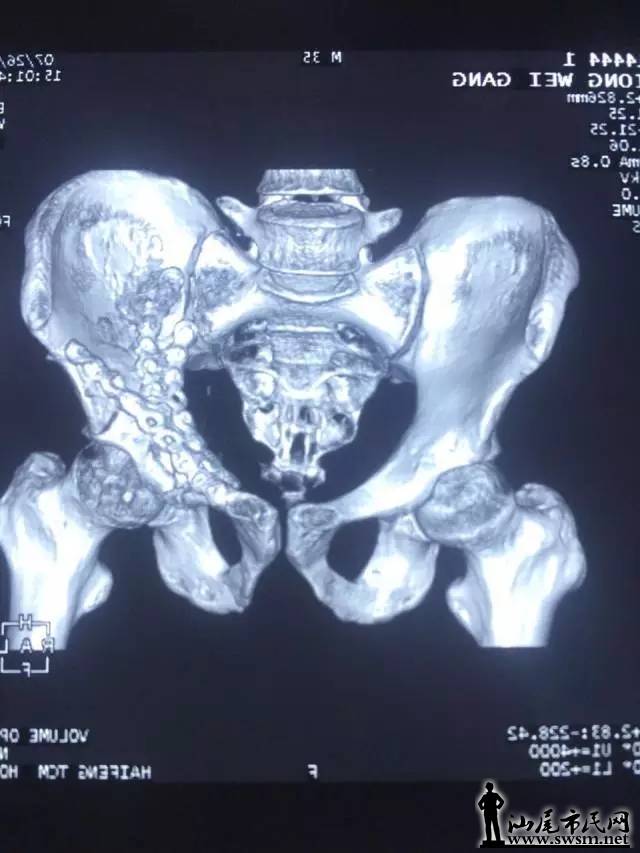

海丰县中医医院骨三科团队,利用3D打印技术,事先将患者的骨盆CT扫描数据输入电脑,再用先进的3D打印机,以1:1比例打印出熊先生的仿真骨盆模型。预先为其设计好最佳的手术治疗方案。                   640.webp.jpg                                                                          ( 上图:术前DR片)                                                                                                                   640.webp (1).jpg       640.webp (2).jpg                                                 (上图:术前CT片)

骨三科团队手术前在仿真骨盆进行虚拟手术,设计好钢板旋转的最佳位置、螺钉植入的最佳方向,并进行钢板、螺钉长度的数据测量,螺钉方向导航模块的设计及钢板预弯等一系列术前体外模拟手术,所有准备工作操练完毕,最后才正式为其施髋臼骨折复位钢板内固定手术。                                     640.webp (3).jpg                                                                                  (上图:虚拟手术,预弯钢板、测螺钉长度等数据)

由于钢板放置最佳位置、螺钉长度等已按照伤者的身体进行过精准的测量,减少了不必要的显露,手术切口仅8厘米;手术中也不需要反复预弯钢板和测定螺钉,使得手术时间大大减少。真正的内固定手术不到1小时,另外前后出血不足600毫升,大大节约血源、减少输血风险等,提高了手术的安全性,减少了伤者的痛苦。                                                                                        640.webp (4).jpg 640.webp (5).jpg 640.webp (6).jpg 640.webp (7).jpg                                                                          从术后复查钢板位置及螺钉植入方向、长度与术前3D打印模拟手术完全匹配,患者术后第二天便可以自行翻身、半坐等,良好的疗效受到了患者及其家属的称赞。